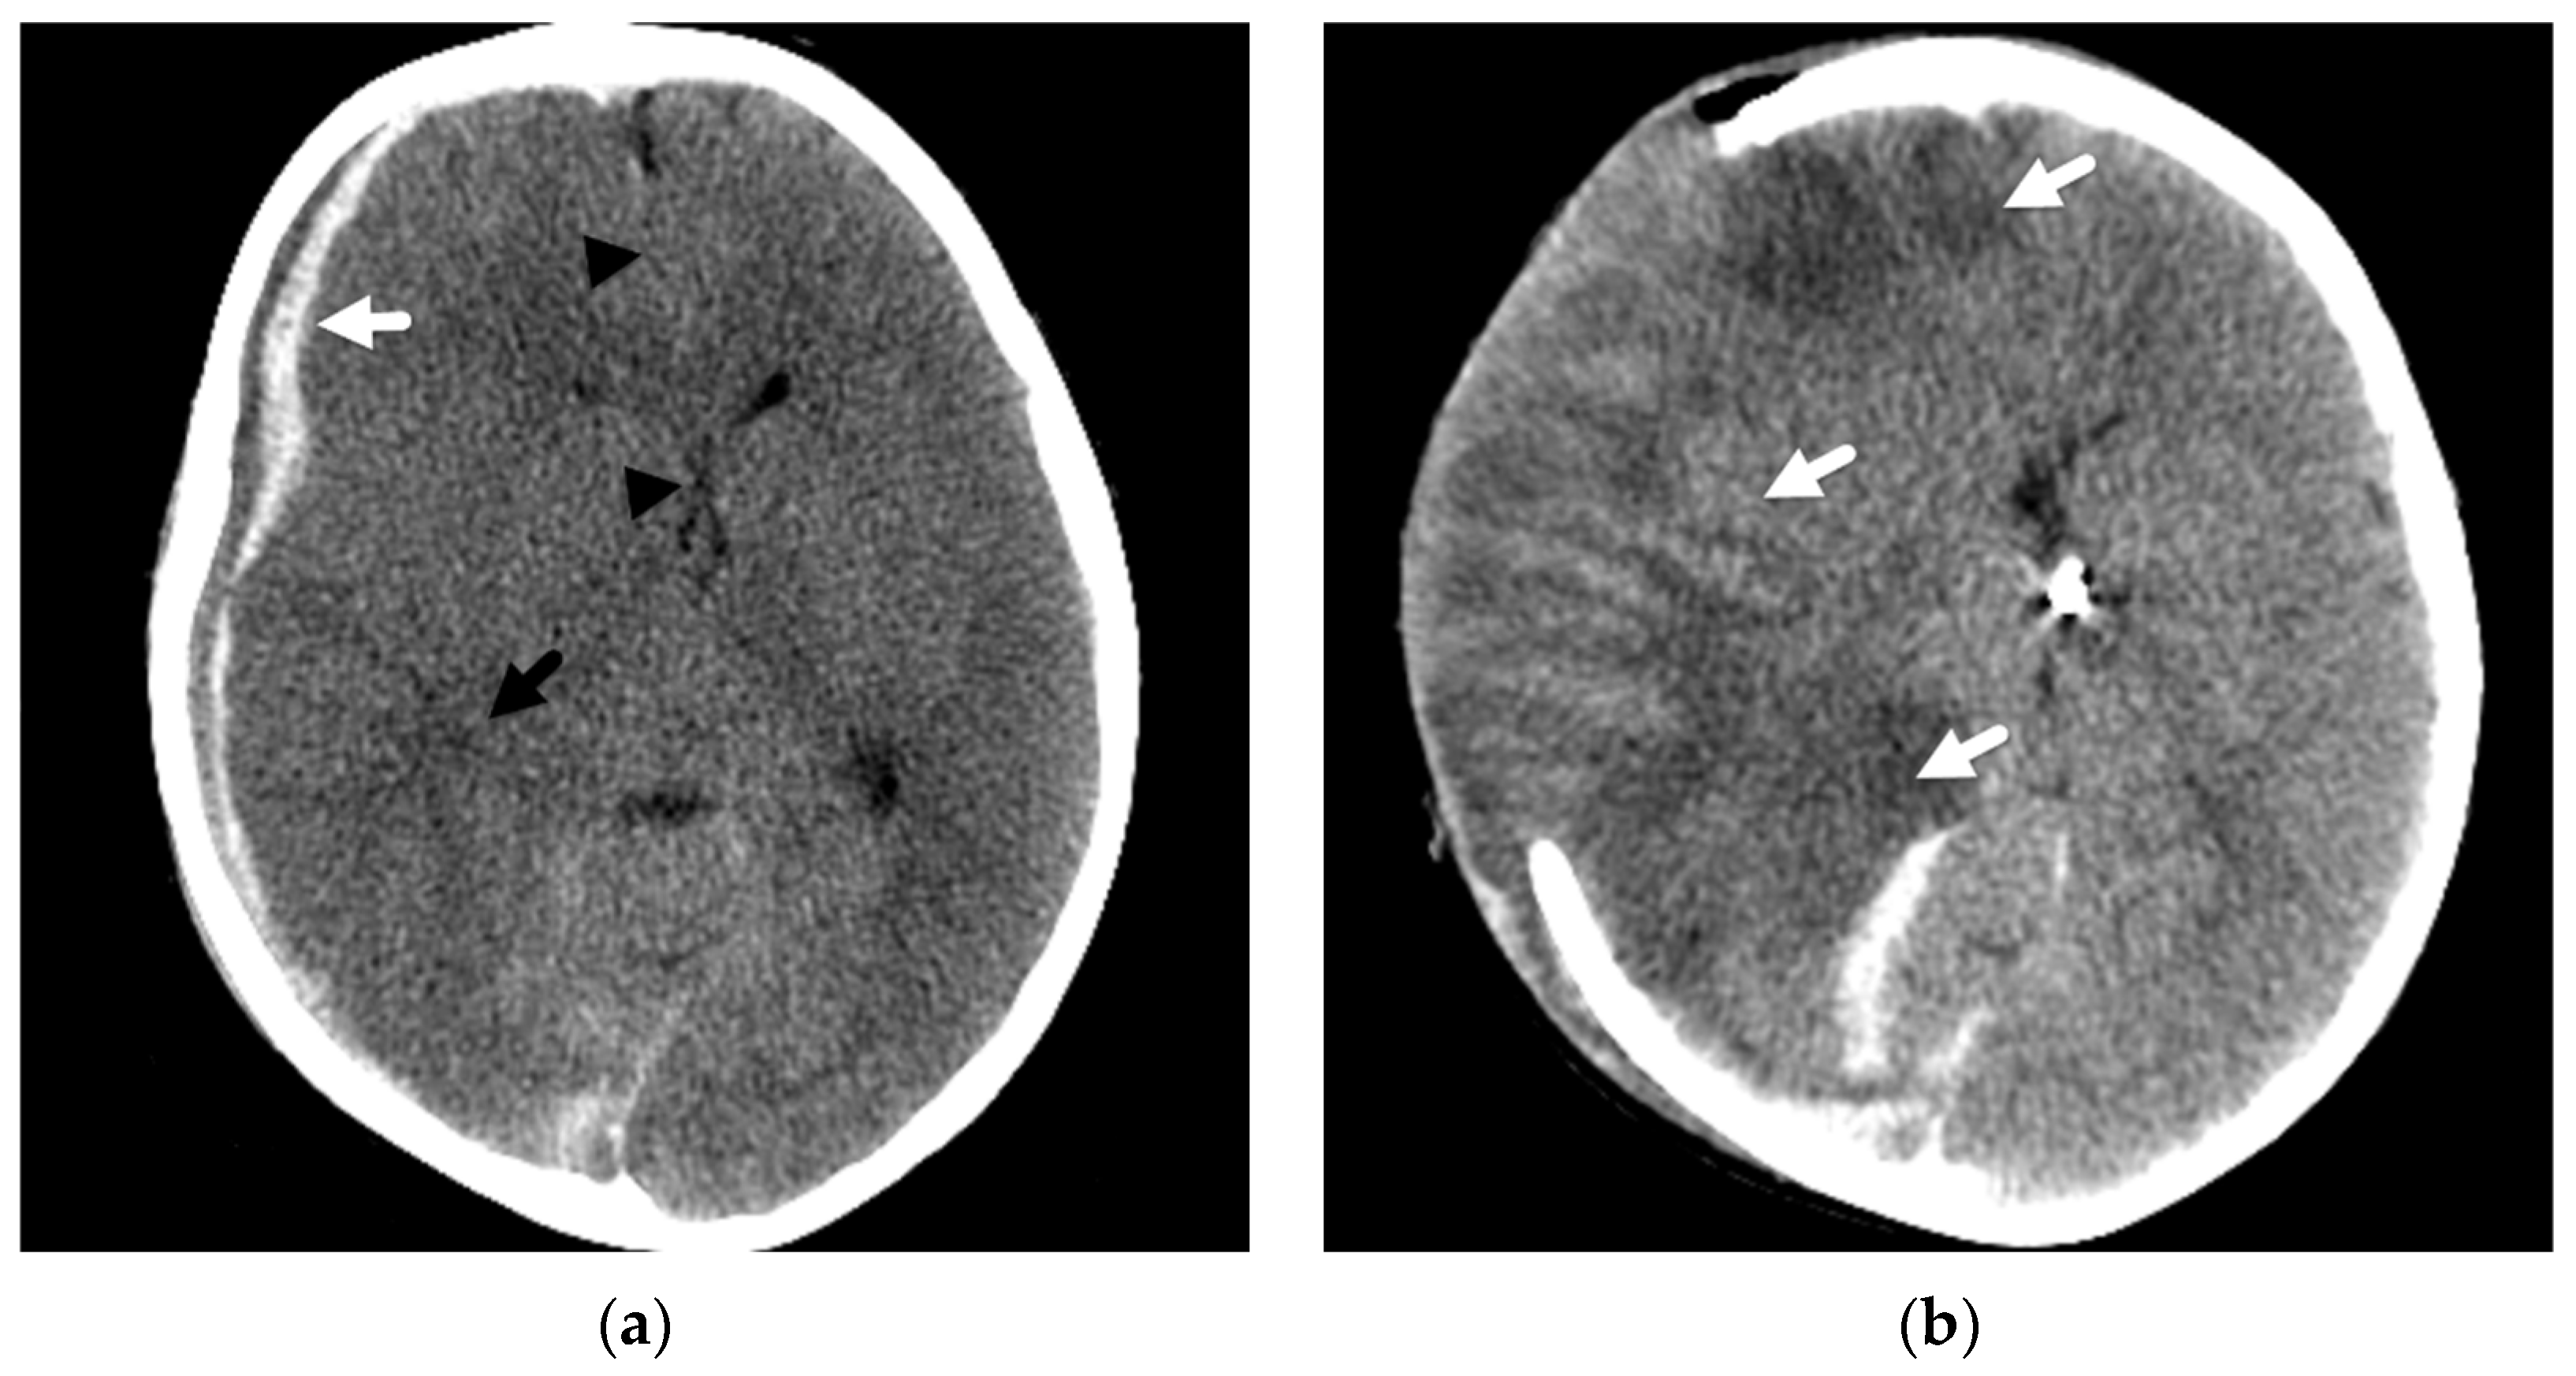

3. Imaging of Diffuse Insults

4. Focal Parenchymal Insults

5. Imaging Evaluation